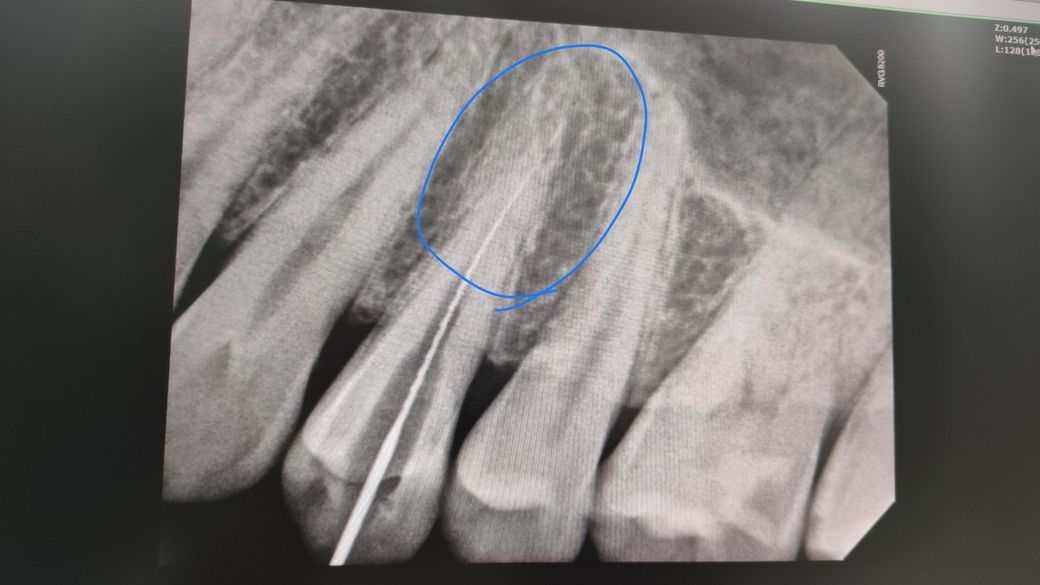

치수염이 생겨서 신경치료를 한달전에 받았는데도 게속 뿌리쪽이 은근히 쑤시는 통증이 있습니다. 가만히있어도 지속적으로 은은하게 기븐나쁜 쑤심이 있어요 저녁에좀더 쑤심이 심해지는거같고

뿌리에 염증이나 크랙같은게 있는거 아닌가 위심되는데

엑스레이 동그라미친 뿌리 부분에 사진보시구 염증이나 크랙이맞는지 확인해주세요 감사합니다.

엑스레이 동그라미친 뿌리 부분에 사진보시구 염증이나 크랙이맞는지 확인해주세요 -> 염증은 보입니다.

엑스레이 상으로는 크랙을 판단할수는 없고 신경치료를 햇는데도 계속 통증이 잇다면 크랙때문에 발치를 하셔야될수도 있습니다.

방사선 사진으로는 뿌리에 있는 금이 보이지 않는 경우가 많습니다 신경치료후에도 불편감이 있다면 재근관치료를 해볼수 있으며 치과보존과 전문의 선생님에게 진료를 받는다면 해당증상을 없앨수 있는 경우도 있습니다.

잔존신경이나 또다른 신경길이 있을 수도 있습니다 미세한 크랙은 엑스레이상 나타나지 않을 수도 있습니다